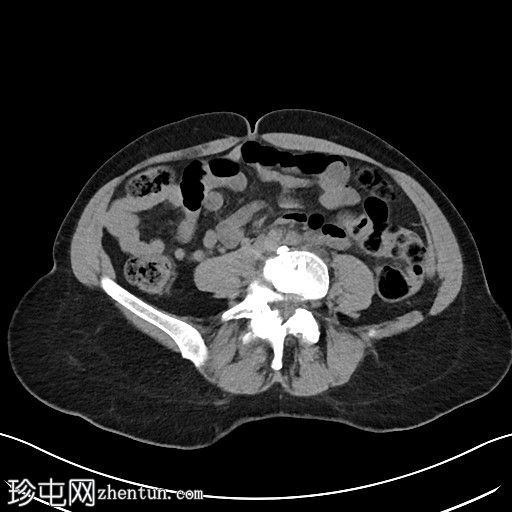

左侧腹膜后可见一巨大囊性肿块,位于左侧腰大肌内侧,紧邻多个手术夹(ALIF手术所用),这些手术夹紧贴囊性肿块后壁。

膀胱已行引流管减压,并被囊性肿块向右侧推移。

子宫和左侧附件在囊性肿块前方保持正常的脂肪间隙,因此附件囊性病变的可能性较小。

左侧输尿管难以辨认,因为它位于囊性肿块下缘后方。

左侧腹膜后巨大囊性病变,符合术后淋巴囊肿。鉴别诊断包括血清肿、尿瘤和脑脊液积聚,但脑脊液积聚的可能性较小。